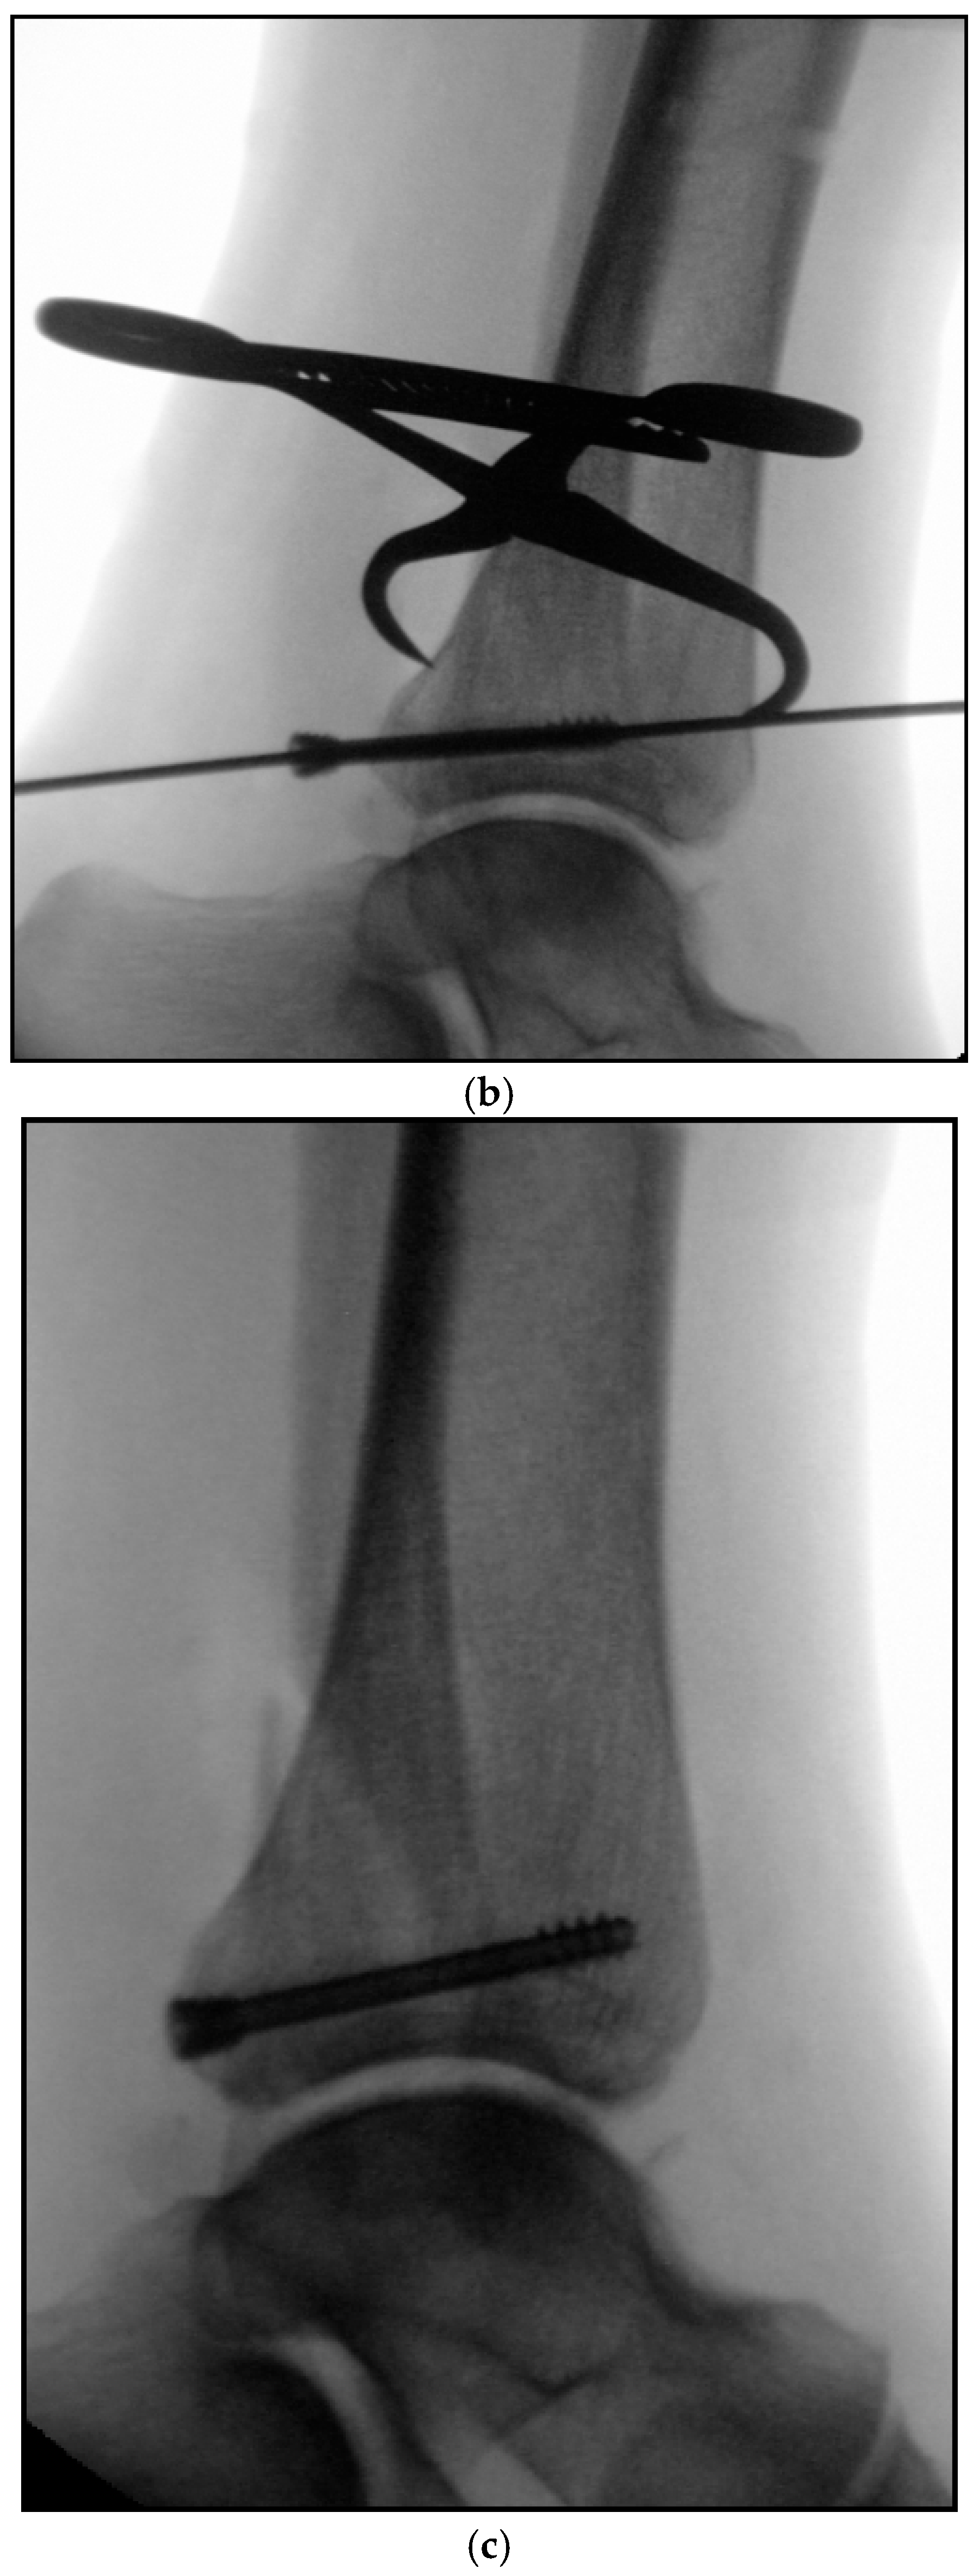

2. Preoperative Diagnostics

3. Intraoperative 3D Fluoroscopic Control